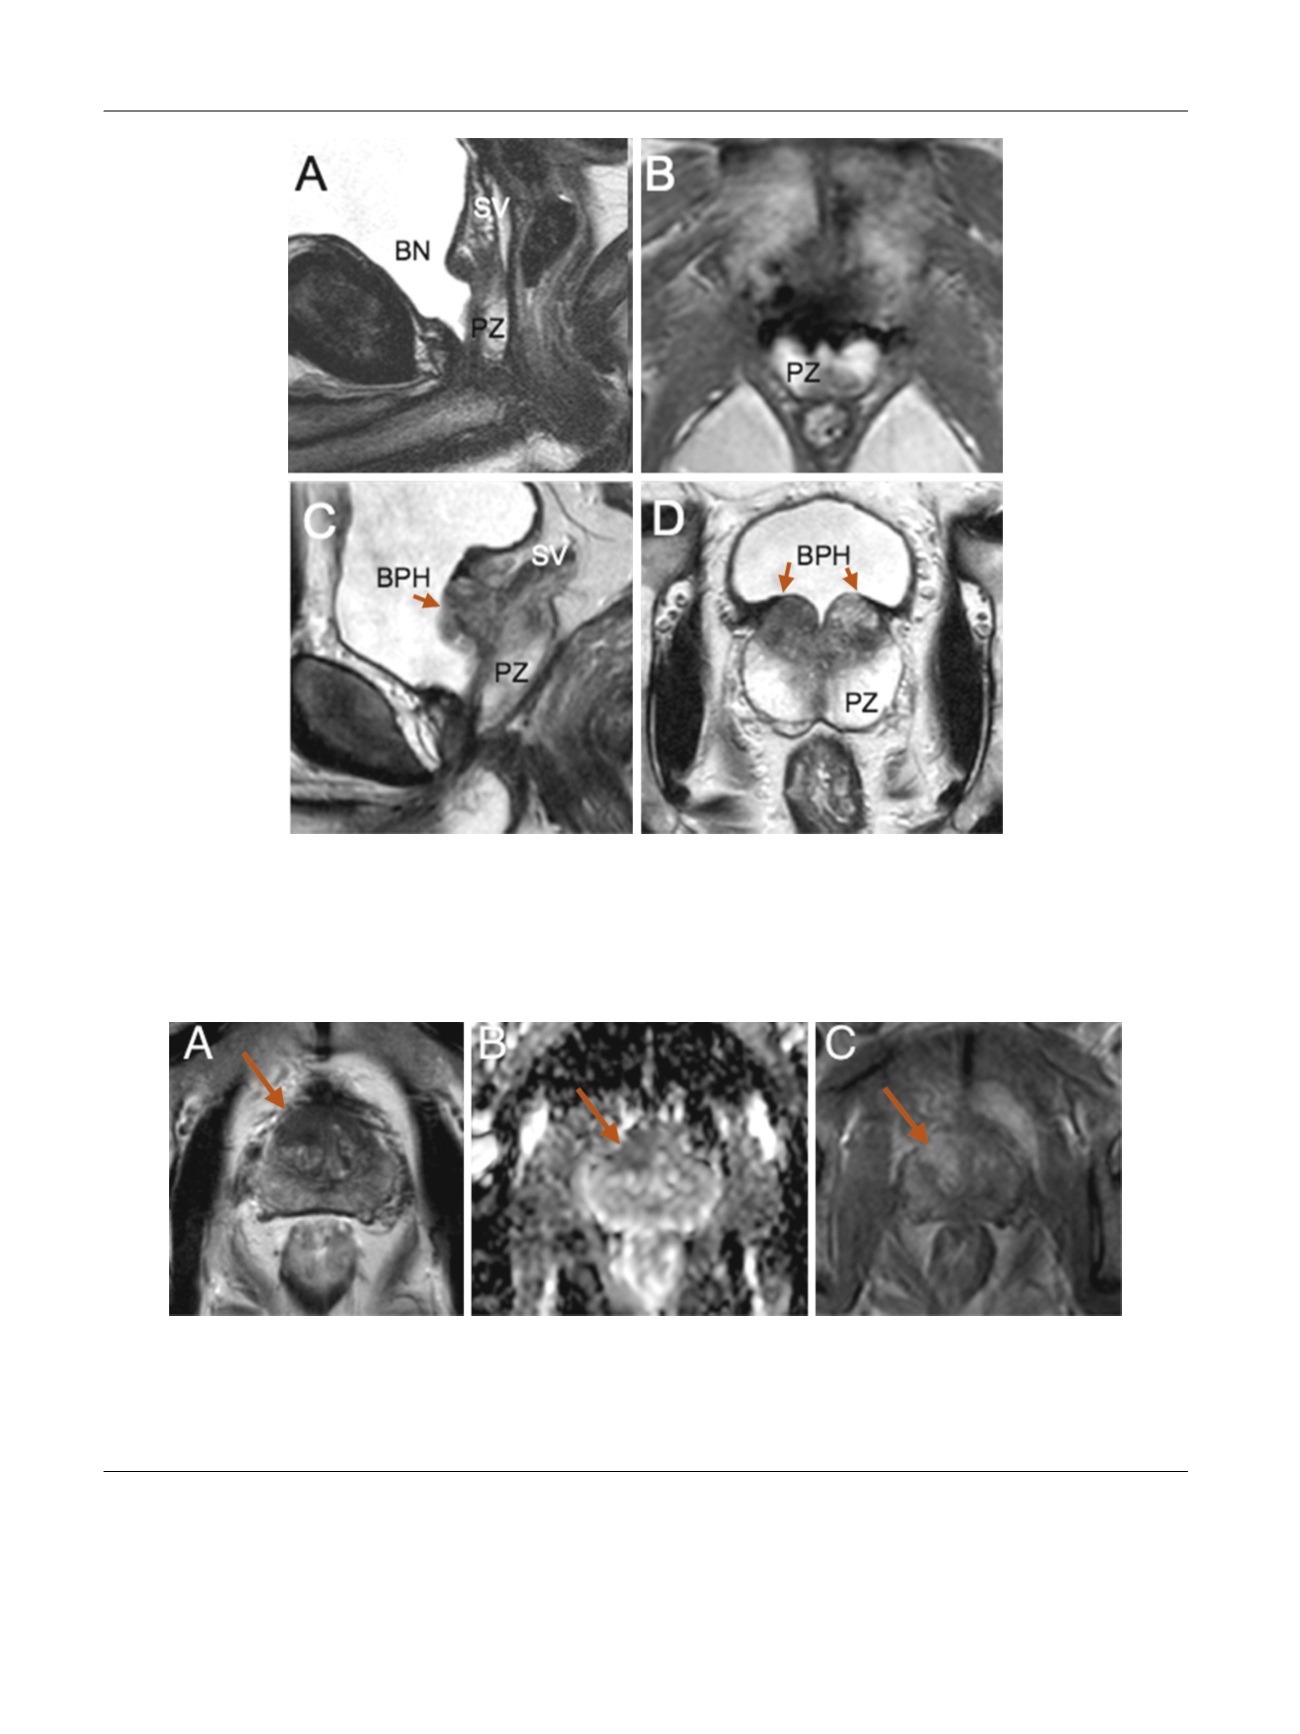

Fig. 4 – Cases 4 and 5 showing postoperative T2 magnetic resonance imaging (MRI) sequences at 6 mo, (a) sagittal and (b) transverse, and at 4 yr, (c)

sagittal and (d) transverse; preserved peripheral zone (arrows) and seminal vesicles. Case 14 (a, b) had stable prostate-specific antigen (PSA) of 0.74 ng/

ml at 6 mo and 0.70 ng/ml at 2 yr. Case 5 had rising PSA of 0.71 ng/ml at 6 mo and 1.34 ng/ml at 2 yr. MRI showed a symmetric area of benign

prostatic hyperplasia recurrence/persistence at the prostate base on each side of the bladder neck that may explain this PSA rise with time. Protocol-

based systematic biopsies were negative, and MRI was nonsuspicious for cancer.

BN = bladder neck; BPH = benign prostatic hyperplasia; PZ = peripheral zone; SV = seminal vesicle.